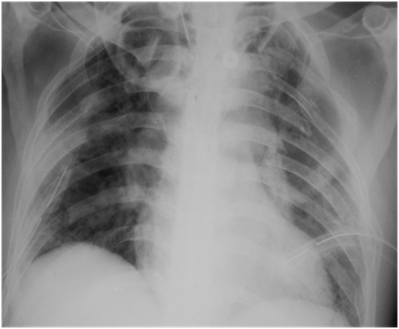

weekly clinical round for undergraduate from 8 to 11 AM during which interpretation of CHEST X rays was done for all cases of cardiothoracic surgery, gived by 2 staf member for 3 months